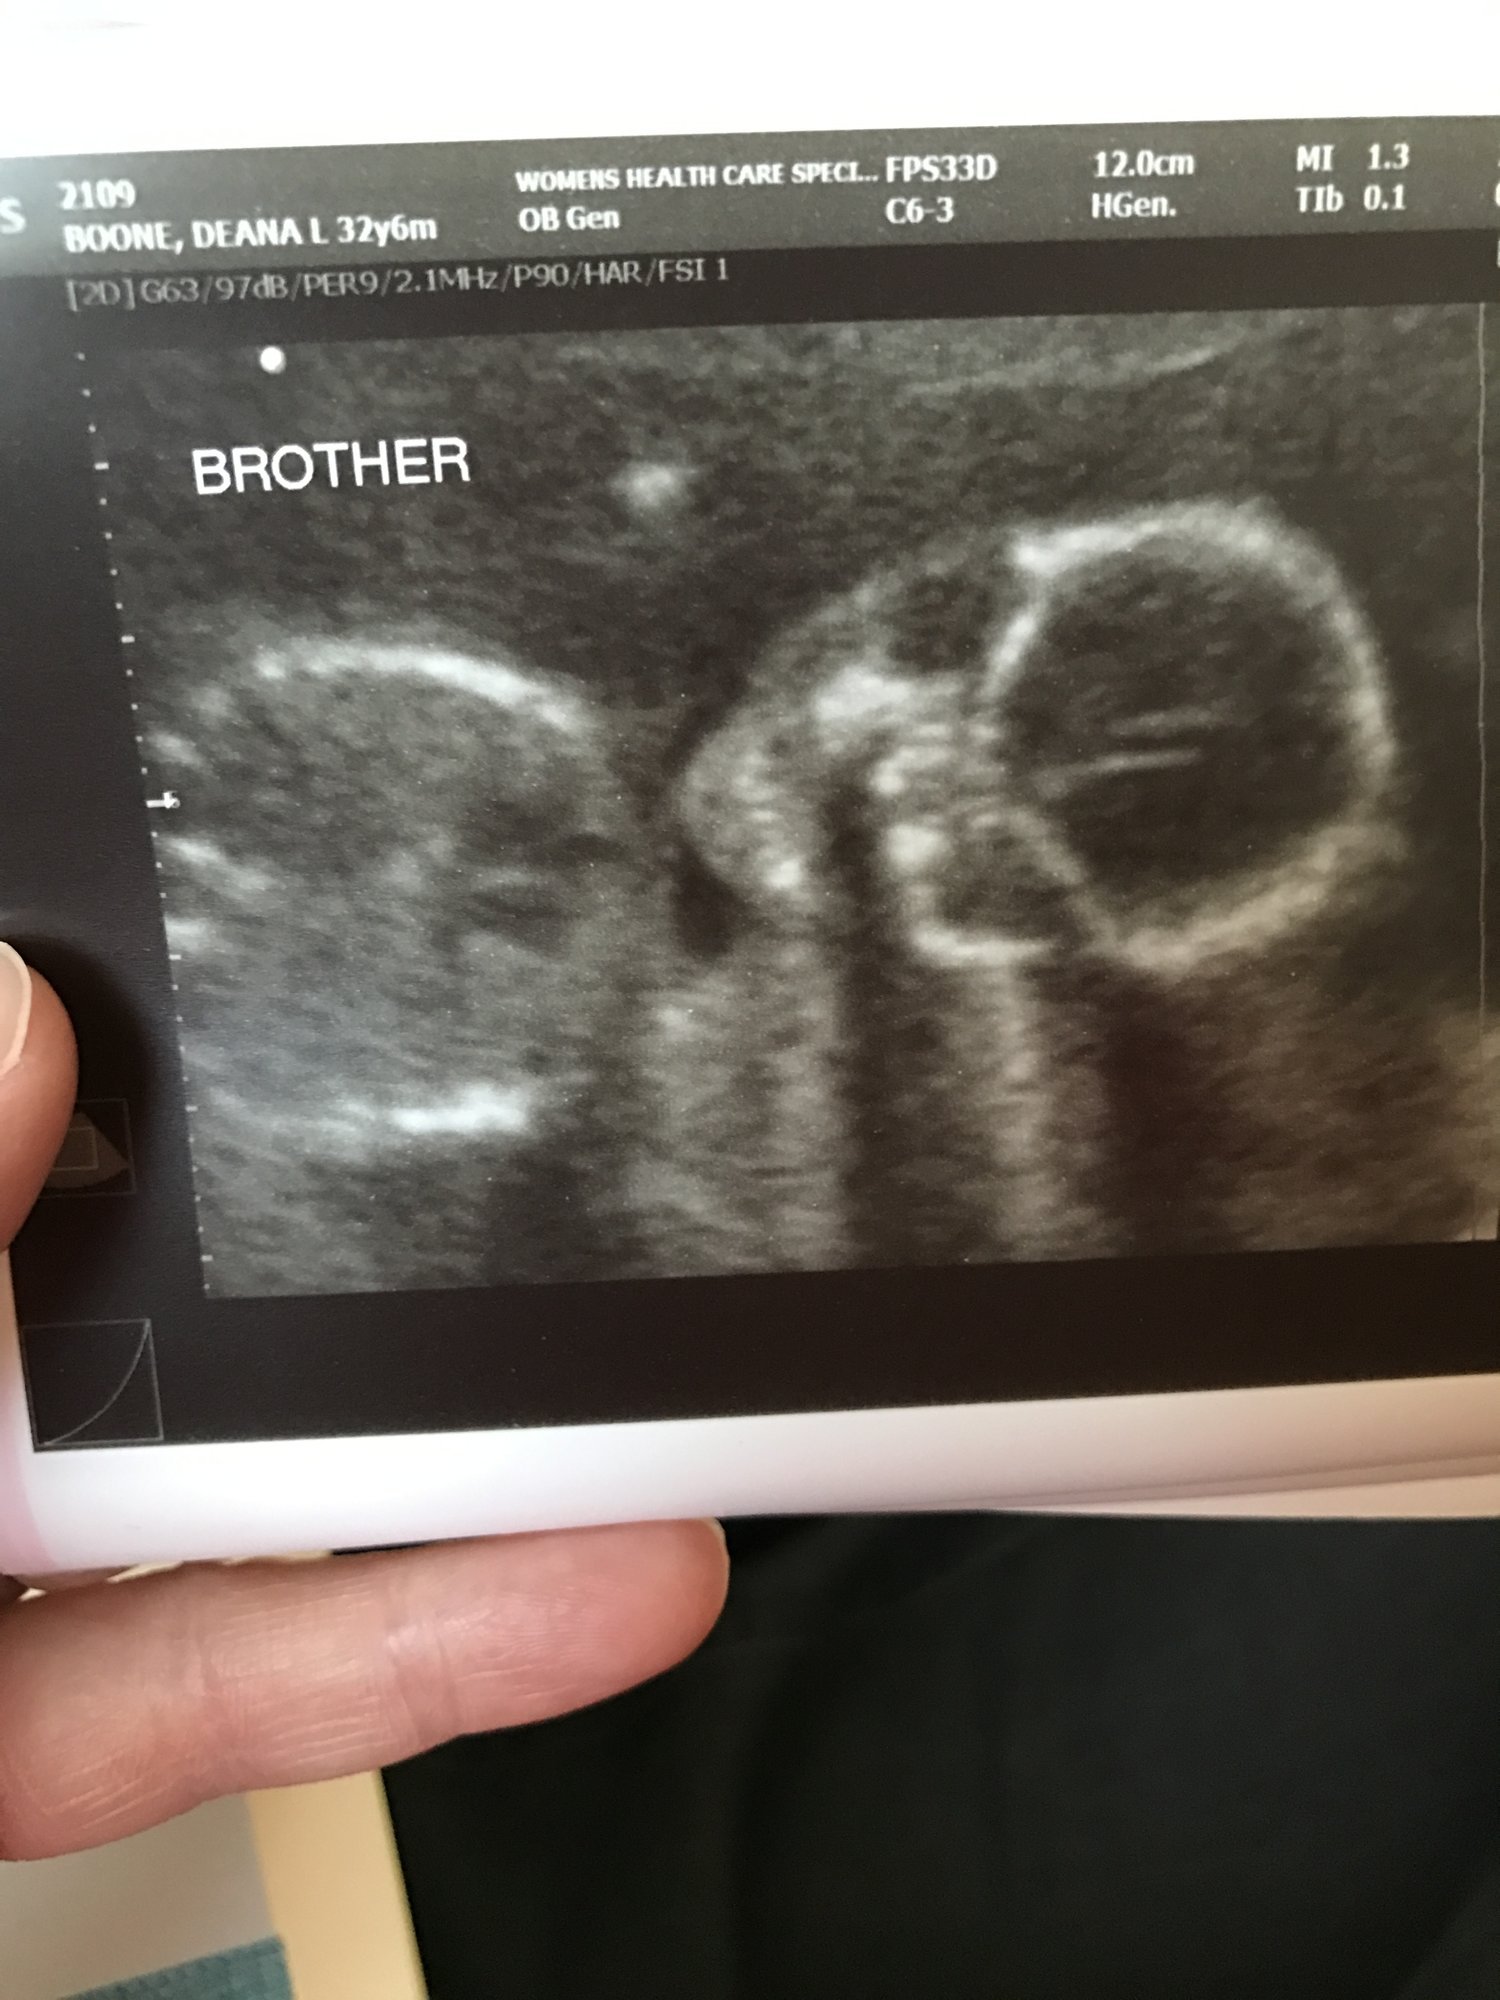

14 weeks today - this was from Monday's 13+5 U/S - Baby A & B